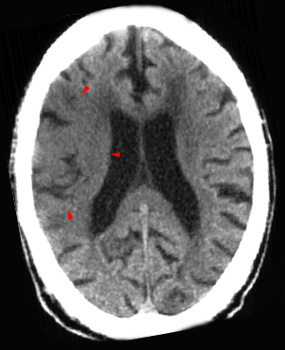

Diffuse Hypodensity and Sulcal Effacement

Diffuse hypodensity and sulcal effacement is the most consistent sign of infarction. Extensive parenchymal hypodensity is associated with poor outcome. If this sign is present in greater than 50% of the middle cerebral artery territory there is, on average, an 85% mortality rate. Hypodensity in greater than one-third of the middle cerebral artery territory is generally considered to be a contra-indication to thrombolytic therapy.